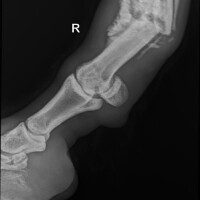

Čim su preuzele brigu o konju obavljen je i prvi korak - rendgensko snimanje noge, koje je obavio Dr. Cik. Snimka je, nažalost, otkrila da je riječ o složenom prijelomu. Uslijedila je potom dobra i jedna ne tako dobra vijest - operacija mu može spasiti nogu, a time i život, no cijena joj je visokih 10.000 eura.

Prije par dana došao je i taj trenutak - nakon uspješne operacije noge, u koju su ugrađene dvije pločice i čak 17 vijaka, vratio se iz Austrije na svoj Brač.